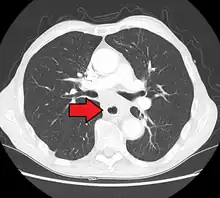

Additional testing is needed to assess how much the cancer has spread (see #Staging, below). Computed tomography (CT) of the chest, abdomen and pelvis can evaluate whether the cancer has spread to adjacent tissues or distant organs (especially liver and lymph nodes). The sensitivity of a CT scan is limited by its ability to detect masses (e.g. enlarged lymph nodes or involved organs) generally larger than 1 cm.[41][42] Positron emission tomography is also used to estimate the extent of the disease and is regarded as more precise than CT alone.[43] Esophageal endoscopic ultrasound can provide staging information regarding the level of tumor invasion, and possible spread to regional lymph nodes.

Contrast CT scan showing an esophageal tumor (axial view)